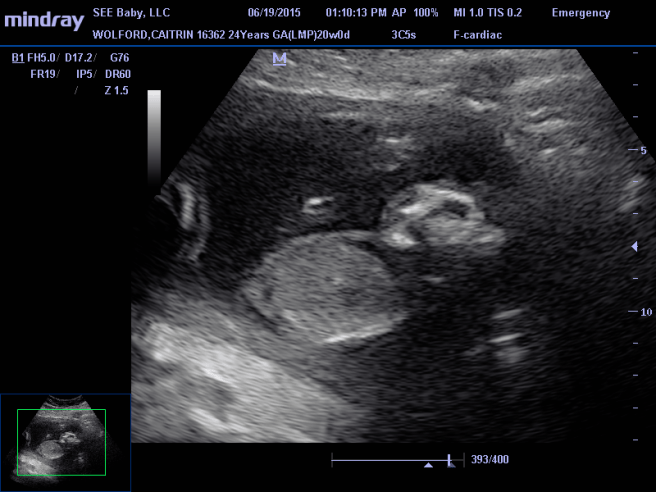

He was very happy we had chosen to keep her and I think excited as well. He told us that he saw this as a real pregnancy and a real baby that deserved just as much care and attention as any other pregnancy. He was not disgusted or annoyed with us keeping a baby that is “incompatible with life” and quite frankly, disagreed with the belief that these babies aren’t important or valuable. He was thrilled with all of the things she can do, and seemed genuinely happy to hear how well she is doing and what a sweet baby she is. We asked him how many babies with anencephaly he had seen go full term (because he has said before that he has seen quite a few babies with anencephaly), he said in 25 years he has seen 10. To be honest, that was more than I was expecting.

We discussed delivery options and he understood our main goal was to see Brielle alive and hold her alive. We talked about how a cesarean would be with him and which incision would be the least traumatizing to my body. The risks are still there, but we agreed a low transverse incision would be best, so I can birth vaginally with my other pregnancies (.2% – 1.5% of uterine rupture). His goals for delivery were exactly what ours were as well. Immediate skin to skin contact, delayed cord clamping (30% of the baby’s blood is the the placenta after delivery so it is best to avoid cutting the cord until the cord stops pulsating), and no restraints during the operation so that I can bond with Brielle. And he made it very clear that she would never have to leave me during the c-section. Vaginal delivery is pretty much however I want to do things, I even get to eat! He told us that it is really too early to decide between the two, and that I may go into spontaneous delivery and take the decision out of our hands, or that I may go full term and then we can schedule a delivery. I appreciated that he wanted to do what was best for us and not what was best for his time or bank account.

He told us that he was open to helping us find treatment and told us that with Brielle we would be the educators to the doctors we come in contact with and he told us we need fortitude, because there is going to be resistance. But he was happy to help and excited to change the way anencephaly is seen. He told us that was our place in life, to bring attention and change to this defect. We agreed around 36 weeks we will see a pediatric neonatologist and discuss treatment options and a plan once she’s born. Which is something David and I will need to be fully educated for. I’ll make an exciting post about this later.